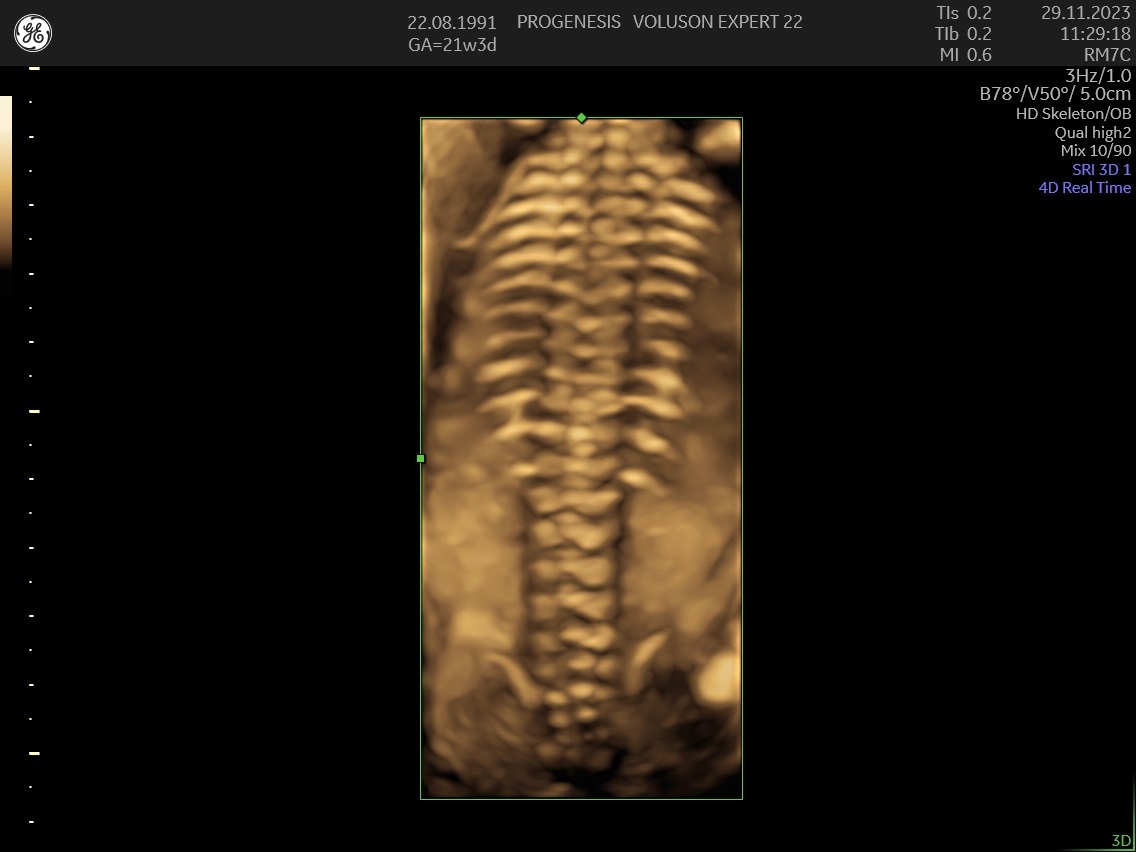

3D/4D LIVE Υπερηχογράφημα

Το 3D/4D LIVE είναι μια νέα τεχνολογία υπερήχων που δημιουργεί εικόνες του εμβρύου σε τρισδιάστατο ή τετραδιάστατο χώρο. Οι εικόνες αυτές είναι πιο ρεαλιστικές από τις παραδοσιακές εικόνες υπερήχων και δίνουν στους γονείς μια πιο ολοκληρωμένη εικόνα του μωρού τους.

Σε πιθανά ανατομικά προβλήματα του εμβρύου μπορούν να βοηθήσουν στην κατανόησή τους από τους γονείς.

Ωστόσο, οι εικόνες 3D/4D LIVE δεν μπορούν να αντικαταστήσουν τις παραδοσιακές εξετάσεις υπερήχων.